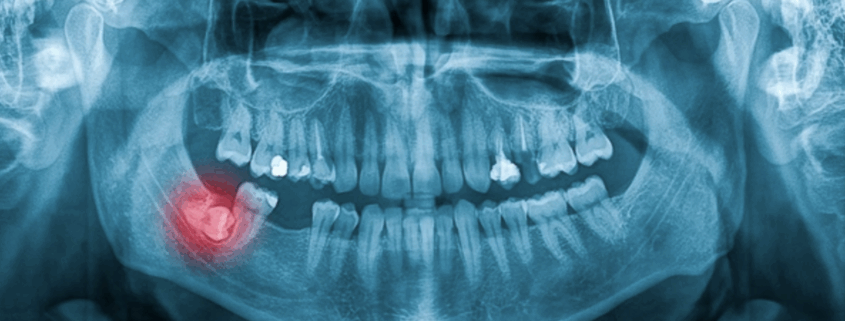

2. Examens préalables

-

radiographie panoramique

scanner 3D si la dent est proche du nerf ou du sinus

Ces examens permettent d’évaluer la position et le risque.